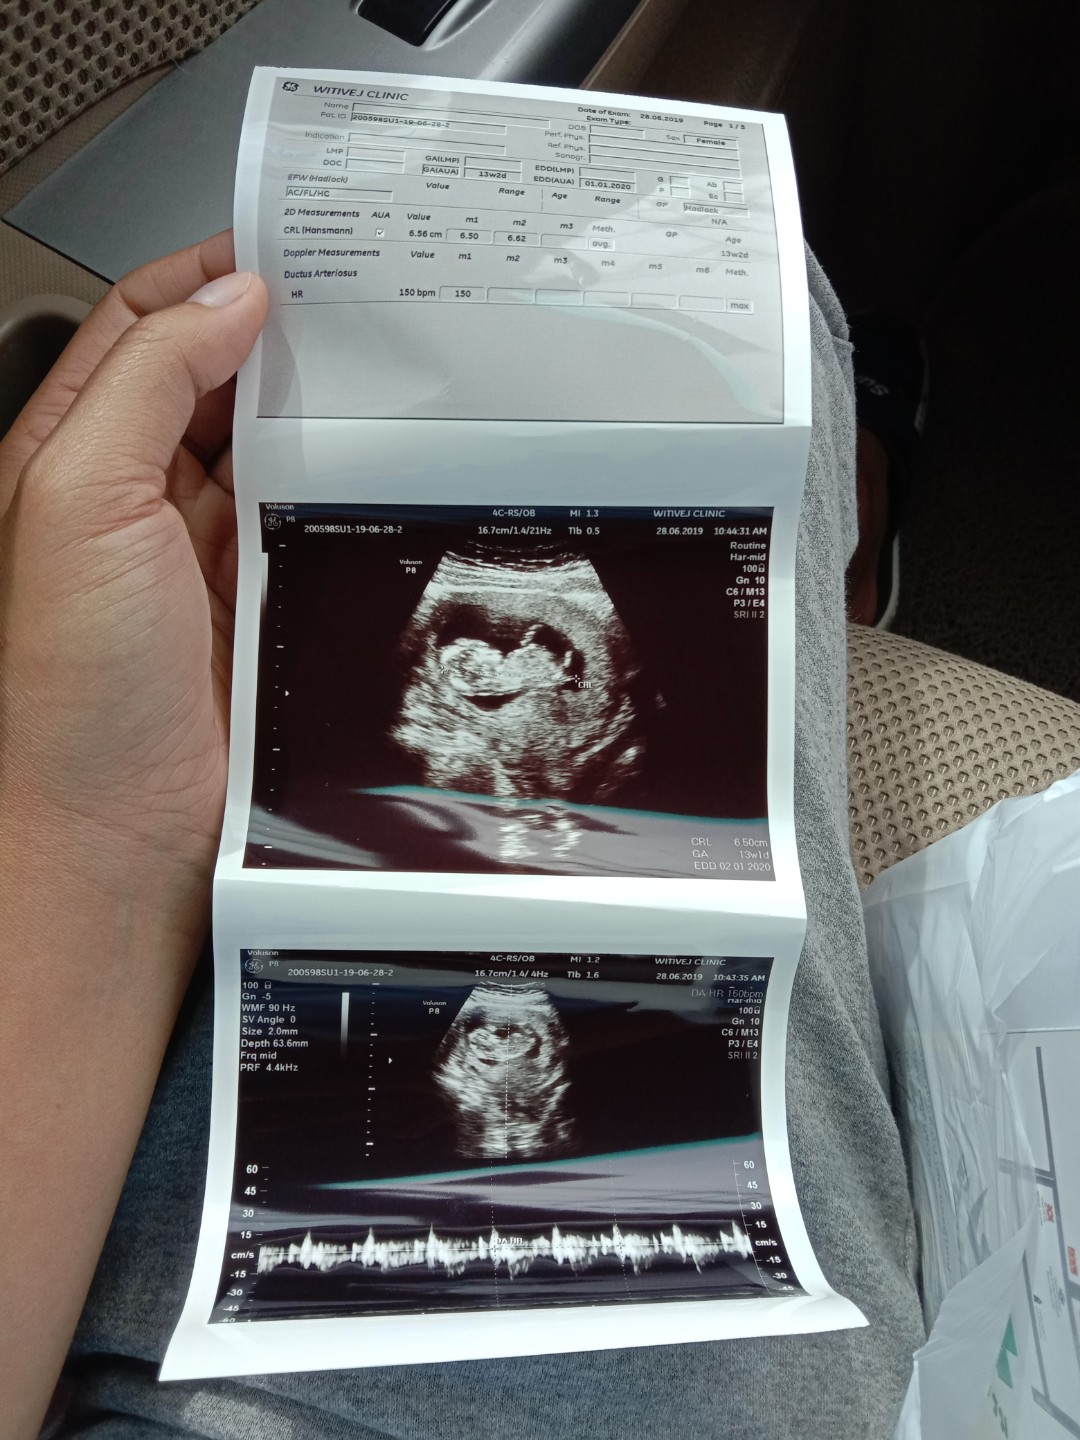

แม่ๆคนไหนมีภาพอัลตร้าซาวด์ประมาณ13วีคบ้างคะ ของเรา13วีค ภาพแบบนี้ค่ะ ดูไม่ออกเลย?

13วีค6วันค่ะแม่